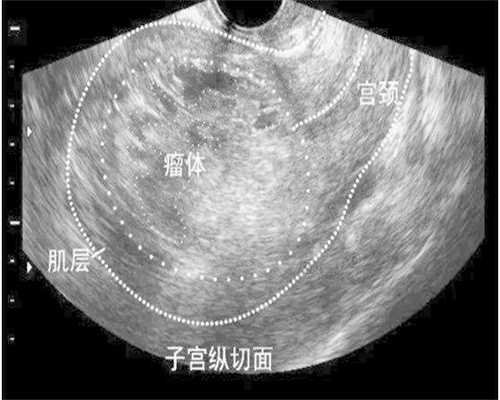

2.妇科疾病治疗费:部分女性身体可能存在影响试管婴儿成功率的疾病,如宫腔粘连、子宫内膜变薄等疾病,需要进行一些额外的治疗。